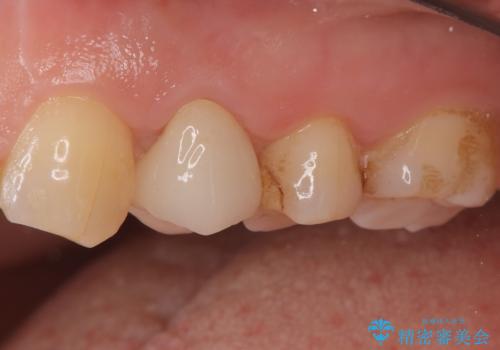

- 他院で昔に根管治療を行ったが、歯肉を押したときの痛みと普段の違和感が残ったままであることを主訴に来院されました。

以前治療した病院では、再根管治療を行わずに歯根端切除のみでの対応を進められたが、治療方針に納得できず当院を受診されました。

治療介入における意思決定が重要となるケースでしたが、患者と相談して①再根管治療→②外科的歯内療法という流れで治療を行いました。

再根管治療を優先した理由としては、破折診断と、当時の治療においてラバーダムや顕微鏡を使用してないとの話があったためです。

結果、根管内にはイスムスにデブリが多く見られたものの破折線は確認できませんでした。再根管治療後、症状の経過を3ヶ月ほど確認しましたが打診、違和感が消失しておらず、外科的歯内療法を行うこととなりました。